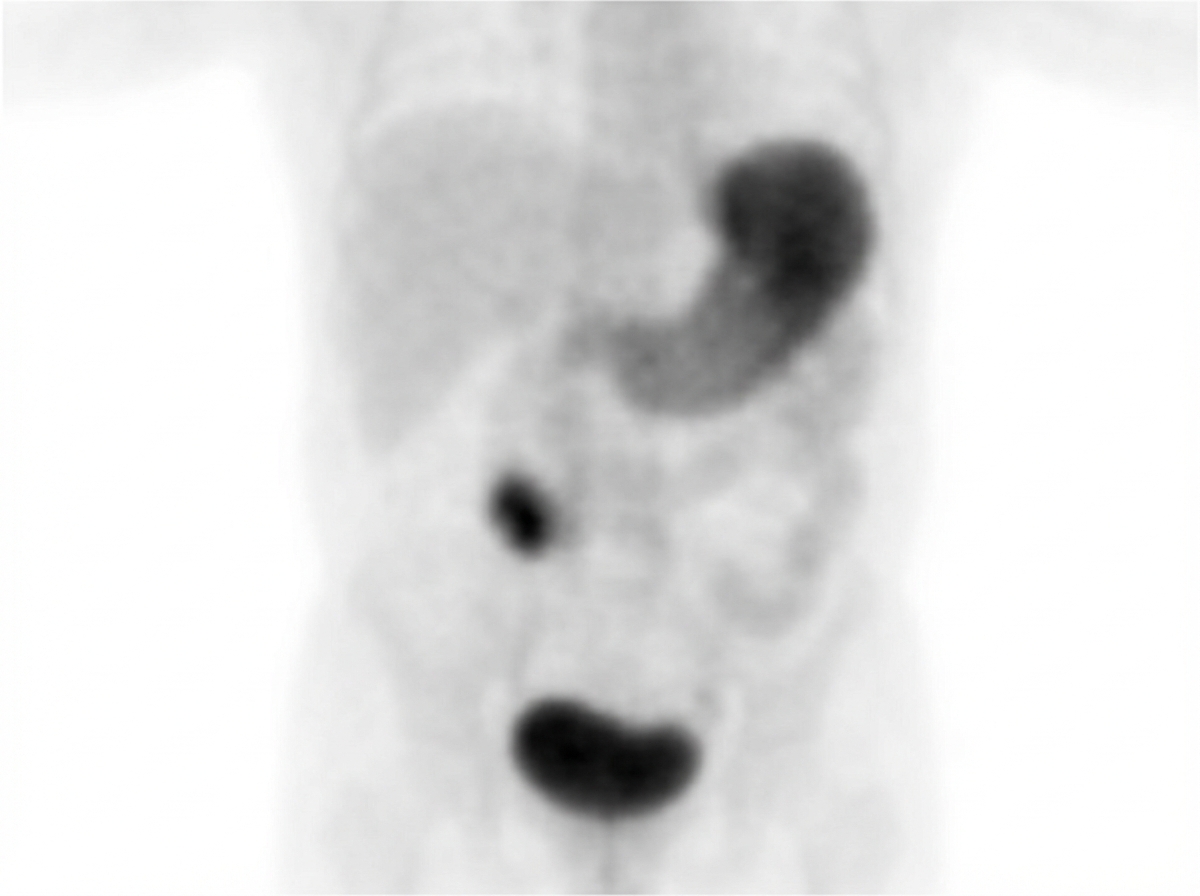

A 2-year-old, previously healthy female presents to the emergency department complaining of 7 hours of 10/10 intermittent abdominal pain, vomiting, and dark red stools. On exam, there is tenderness to palpation in the right lower quadrant and high-pitched bowel sounds. Technetium-99m pertechnetate scan was performed (Image A). Which of the following is true about this patient's condition?